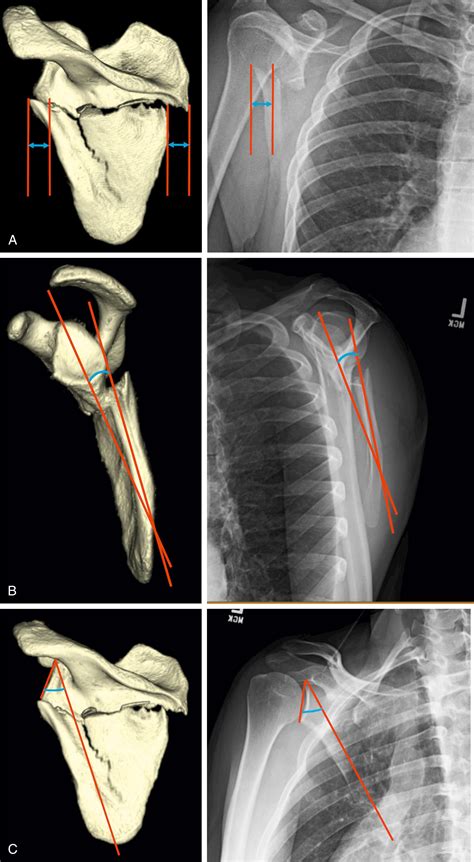

Here is an image illustrating scapular winging:

Scapular Winging